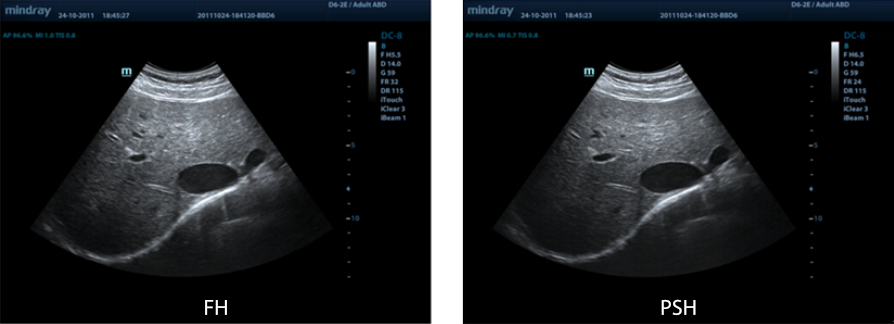

PSHI? (Phase Shift Harmonic Imaging)

Purified Harmonic Imaging for better contrast resolution providing clearer images with excellent resolution and less noise.

iBeam?

Use multiple scanned angles to form a single image for enhanced contrast resolution and improved visualisation.